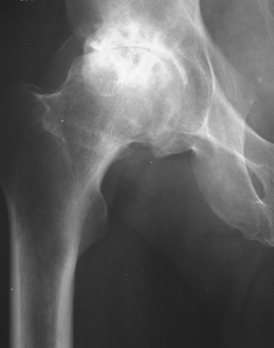

Η οστεοαρθρίτιδα του ισχίου στα πρώιμα στάδια αντιμετωπίζεται με αντιφλεγμονώδη και χονδροπροστατευτικά φάρμακα, δυστυχώς με φτωχά αποτελέσματα. Οι συντηρητικές θεραπείες όπως τα φάρμακα, η φυσικοθεραπεία, τα υαλουρονικά υψηλού μοριακού βάρους και οι βιολογικοί παράγοντες ( stem cells) έχουν αποτέλεσμα στα αρχικά και μεσαία στάδια της πάθησης.